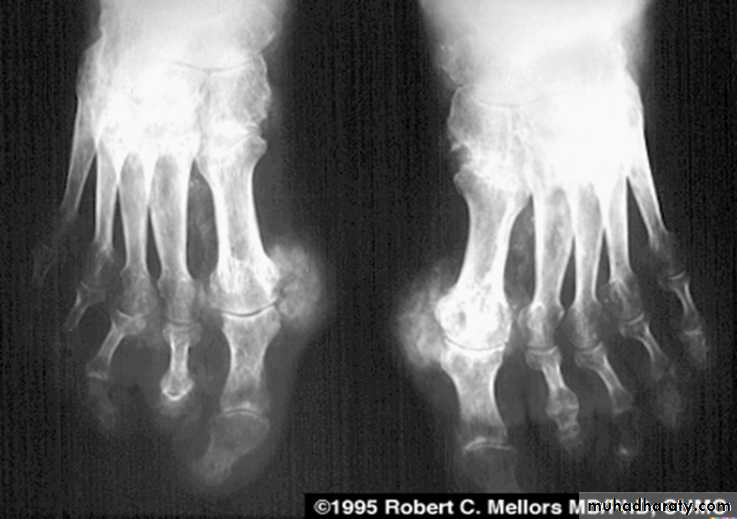

RHEUMATOID ARTHRITIS

Female:male = 3:l

Radiographic features:Early changes

* Peri articular soft tissue swelling (edema, synovial congestion)

*Peri articular osteoporosis in symmetrical distribution (hallmark)

* Preferred sites of early involvement

Hands: 2nd and 3rd MCP joint

Feet: 4th and 5th MTP joint

Late changes

*Erosions (pannus formation, granulation tissue) first attack joint portions in which protective cartilage is absent (i.e., capsular insertion site).

* Erosions of the ulnar styloid and triquetrum are characteristic.

* Subchondral cysts formation results from synovial fluid, which is pressed into bone marrow through destroyed cartilage.

Subluxations , Carpal instability and ulnar deviation .

* Fibrous ankylosis is a late finding.

Rheumatoid arthritis. Bilateral changes are fairly symmetrical. Soft-tissue swelling is demonstrated, especially over the ulnar styloids. Erosions are demonstrated at the carpus, distal radius and ulna, with joint space narrowing and collapse of bone. Metacarpophalangeal erosions are also seen associated with joint space narrowing. There is a swan-neck deformity of the right fifth distal interphalangeal joint

Gross rheumatoid arthritis at the carpus with ulnar deviation,

subluxation and joint narrowing at the metacarpophalangeal joints.Boutonniere deformities are present at the index and little fingers.